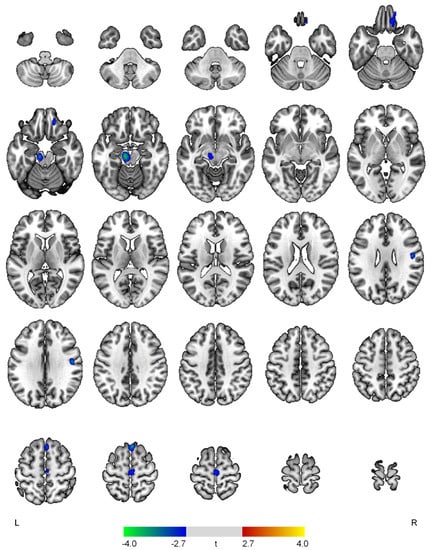

| Positive correlations with the apathy domain | ||||

| None | ||||

| Negative correlations with the apathy domain | ||||

| R superior frontal gyrus | 3.74 | <0.001 | 138 | 4, 26, 64 |

| L midbrain | 3.69 | <0.001 | 265 | −10, −20, −16 |

| R postcentral gyrus | 3.33 | 0.001 | 111 | 48, −10, 30 |

| R medial orbital gyrus | 3.01 | 0.002 | 177 | 16, 40, −22 |

| R precentral gyrus | 2.89 | 0.003 | 156 | 2, −20, 64 |